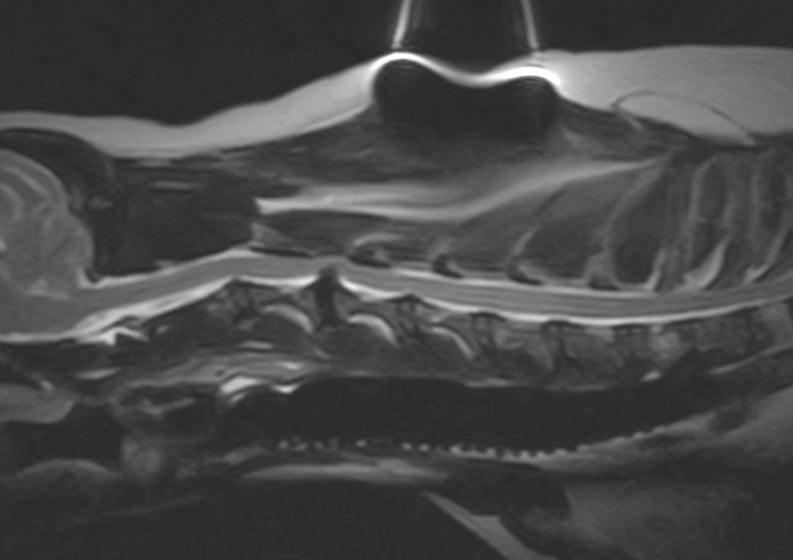

■ MRI検査

第5-6腰椎間で右側神経根が腫大し、脊柱管内に連続した腫瘤病変が認められました。脊髄および馬尾神経は右側から重度に圧迫されていました。

MRI検査所見

MRI 1